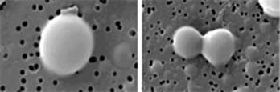

Primo经络管的超微型细胞“活卵(左图)”在分裂的过程(右图)。“活卵”具有其它细胞没有的完全不一样的细胞特性。 |